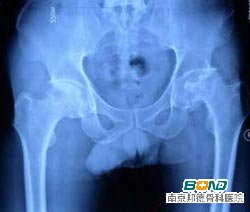

(三)影像学检查:激素型股骨头坏死可借助X线检查,若是无法得出结果,则应进行MRI和CT检查。专家指出,MRI对于激素型股骨头坏死的早期变化比较敏感,因此影像学是很重要的。